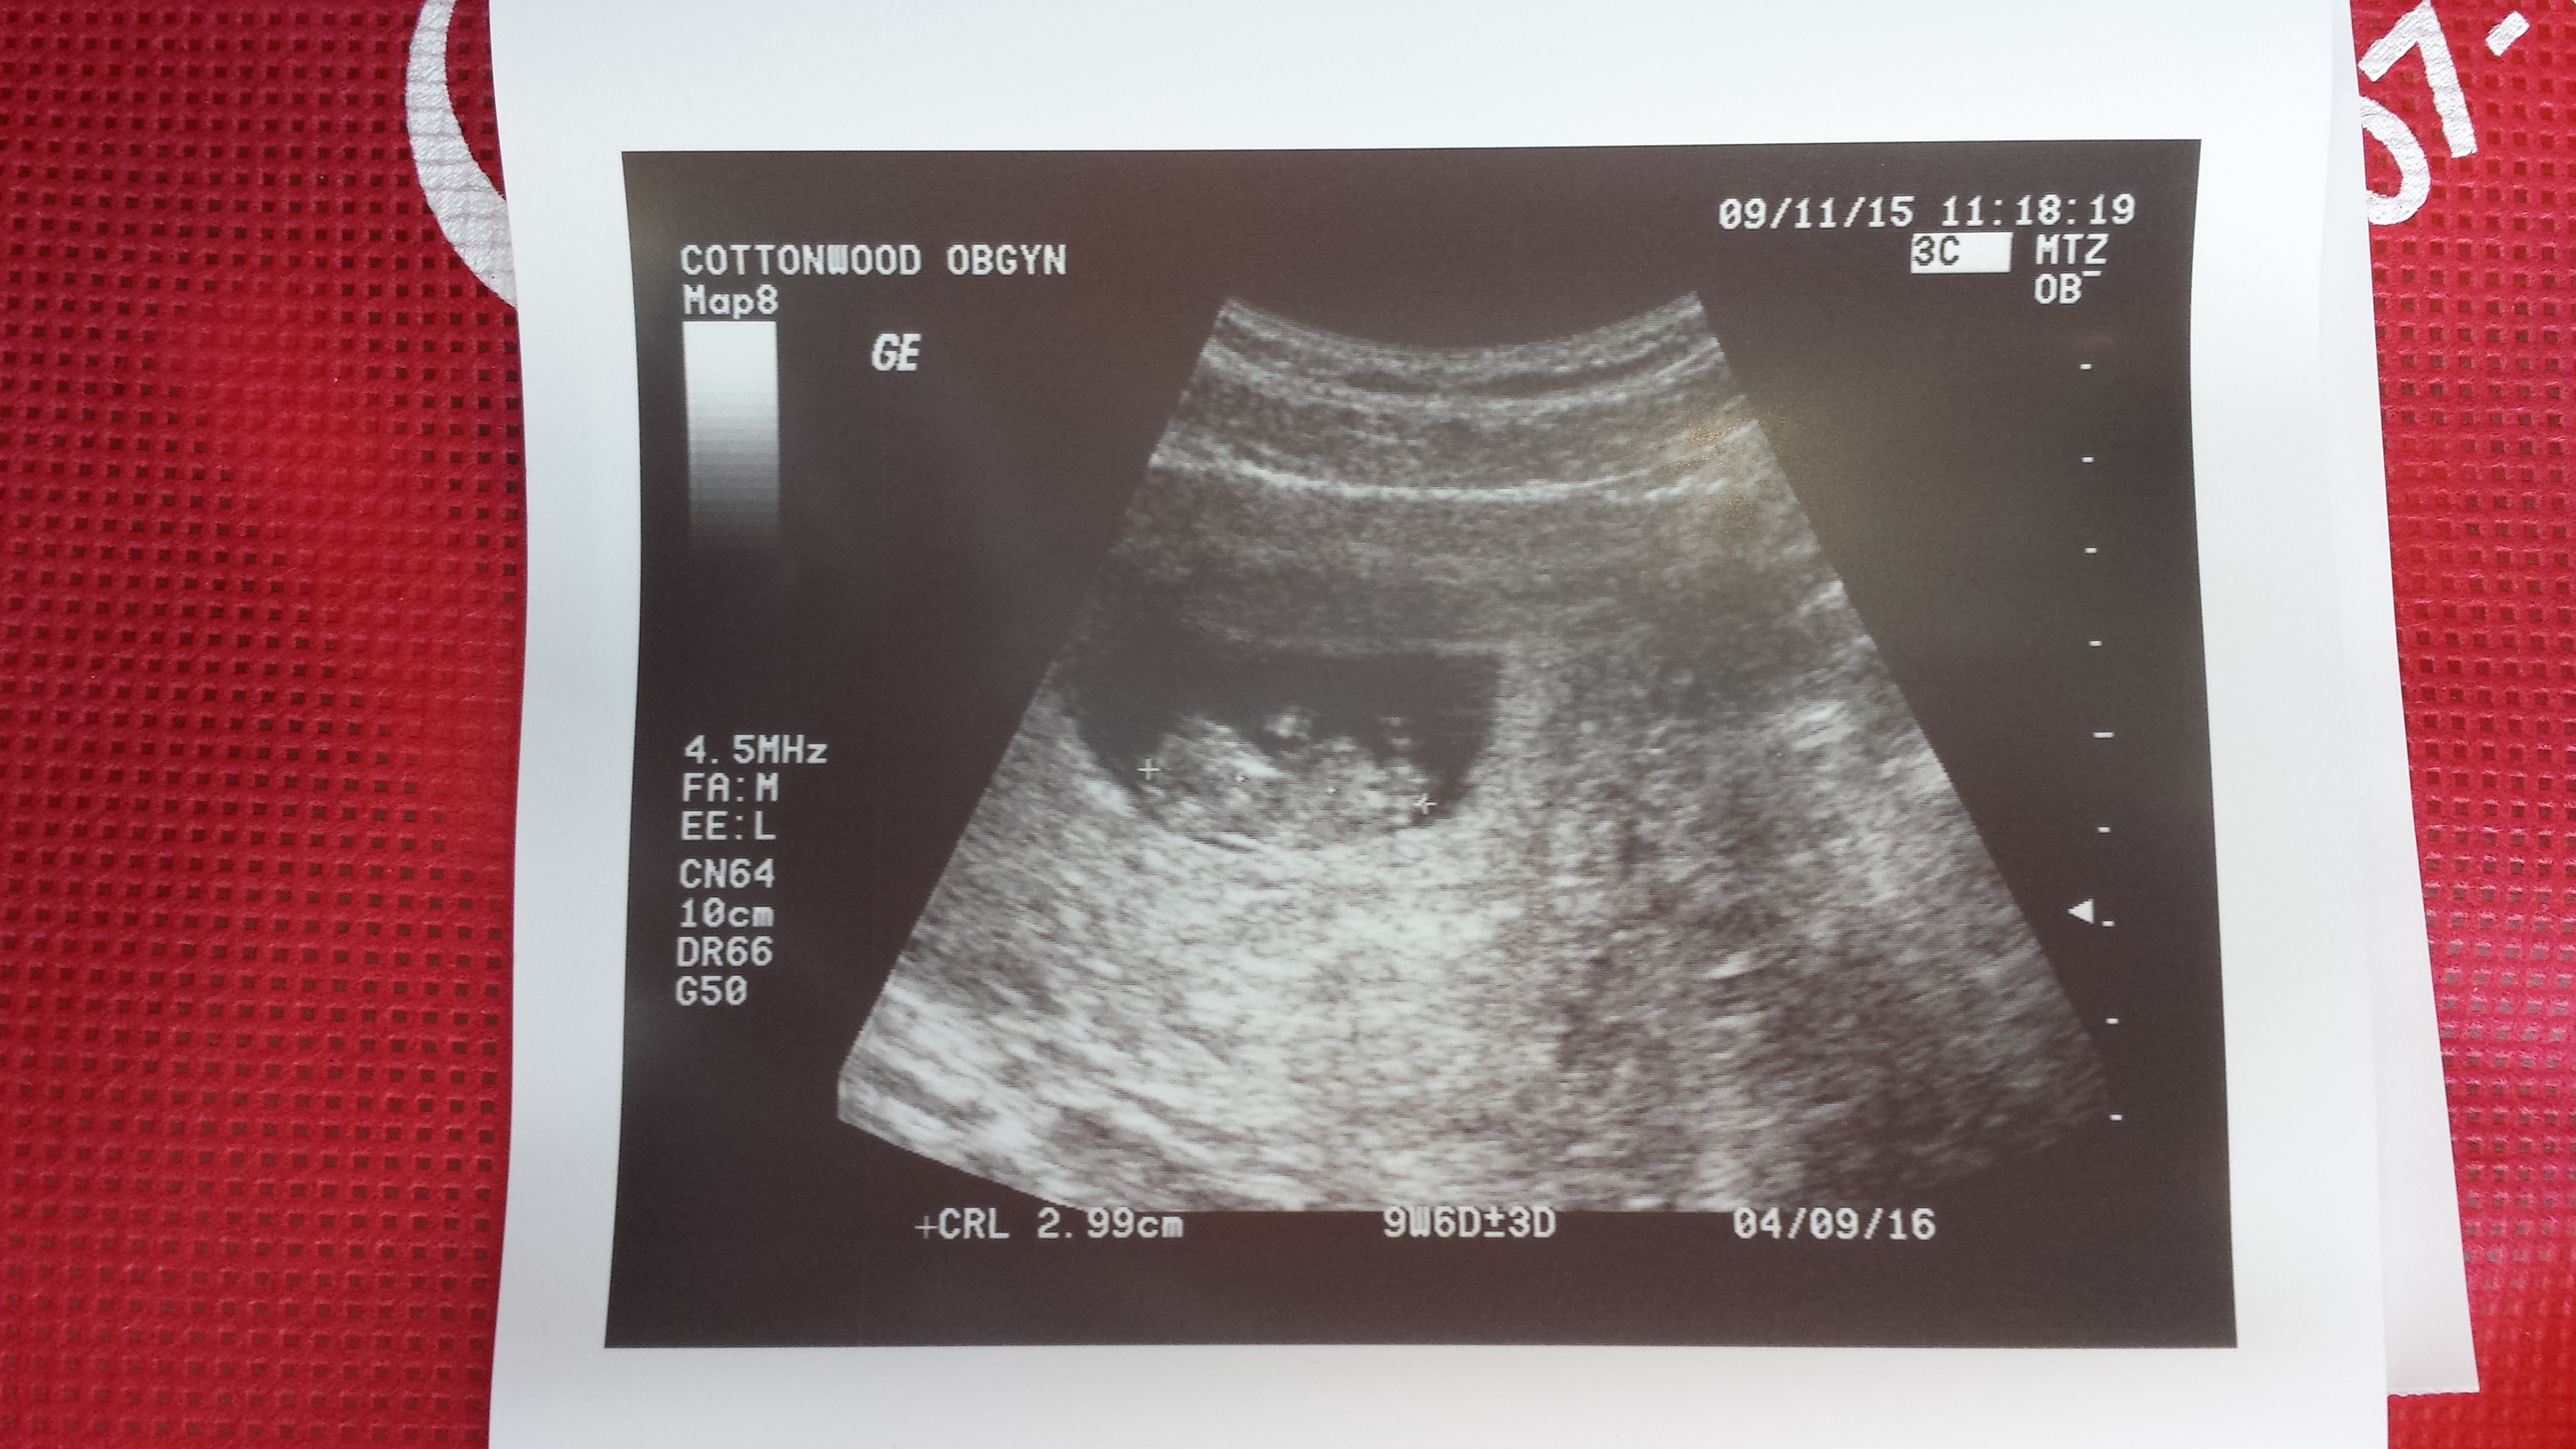

• I was 9W 6d during this ultra sound... Now I'm 10w and 3d